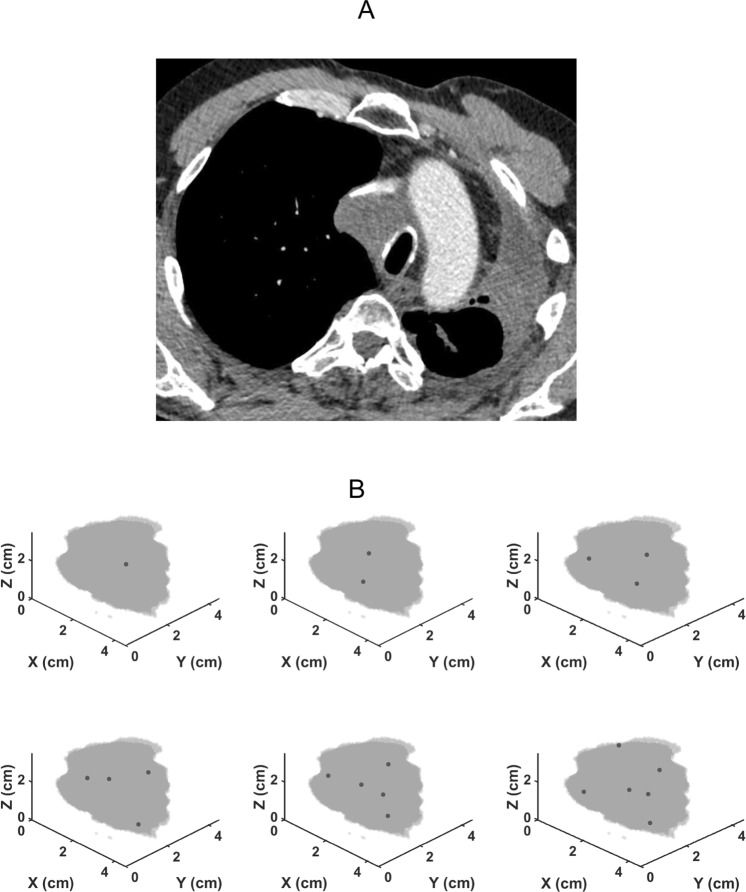

Figure 3 shows renditions of the lung tumor in the patient we studied along with the optimal locations of cisplatin injection sites for 1 to 6 injections calculated using the computational model with the values of , and given above. Note that a single injection is optimally located close to the middle of the tumor while multiple injections are distributed in a balanced way thoughout the tumor mass, as one would expect intuitively. The major benefit of multiple injections, however, is evident in Fig. 4 which shows the total cisplatin dose required to kill all tumor cells as a function of the number of injections. This dose decreases by more than 3 orders of magnitude in going from 1 to 5 injections. Relatively little additional dose reduction is achieved by going to 6 injections, however.

Figure 3.

(A) Axial CT image demonstrating a right paratracheal lung cancer, occurring in the prior radiation field. (B)Three-dimensional reconstructions of the tumor showing the optimal locations for 1 to 6 injections of cisplatin.

The most important finding of our study, however, is the enormous apparent benefit of apportioning a given dose of cisplatin between a number of well-placed injections rather than delivering the entire dose into a single central location, as shown in Fig. 3. Indeed, our model predicts that the dose of cisplatin required to kill a given fraction of tumor cells using 5 injections can be 3 orders of magnitude less than that required for a single injection (Fig. 4). At 6 injections we appear to be approaching the point of diminishing returns, but these results provide compelling evidence that EBUS-TBNI should not be limited to a single injection site in the treatment of lung cancer. This conclusion is further supported by the results shown in Fig. 5 which indicate that increasing the number of injections has a marked effect on the robustness of treatment efficacy in the presence of variations in the local lethal concentration of cisplatin; 5 or more injections are predicted to be almost uniformly efficacious over the range of studied while a single injection is relatively fragile in this respect. Of course, these results are predicated on the cisplatin injections being delivered at the optimal sites predicted by our model. On the other hand, the locations of these optimal sites are distributed roughly uniformly throughout the body of the tumor (Fig. 3). It may therefore be that empirical placement of injections guided simply by the principle of uniform distribution will be close enough to optimal that most of the predicted gains of multiple injections will be realized.